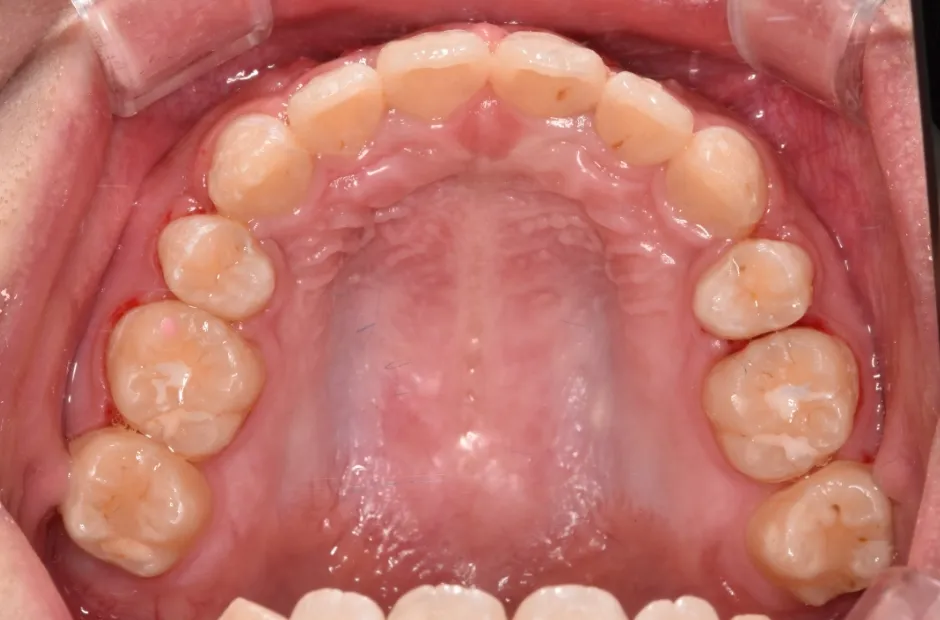

ゆがみ(左右非対称)

| 診断名・主訴 | ゆがみ(左右非対称) |

|---|---|

| 年齢・性別 | 20歳・女性 |

| 治療期間・回数 | 2年半 30回 |

| 治療に用いた主な装置 | 急速拡大 アンカー |

| 抜歯部位 | 左右上5番 |

| 治療費 | 70万円(税抜) |

| リスク・副作用 | 装置による違和感・疼痛・歯肉退縮・歯根吸収・虫歯のリスクなど |

治療後